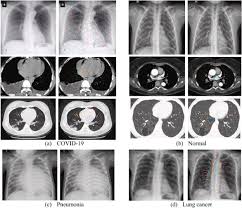

Bronchitis and pneumonia both affect the lungs and share some common symptoms, but they are different diseases that require different treatment. If you have a loved one dying of lung cancer, you will observe many of these signs of dying. In both cases, you may have. Cancer and pneumonia are also related because the treatment for cancer can sometimes lead to pneumonia. Physical changes during the final stages of lung cancer can be related to the tumor in the lungs, the spread of cancer to other parts of the body, or due to the terminal stages of cancer in general.

Double Pneumonia Symptoms Treatment And Prognosis from post.healthline.com In both cases, you may have. It took about 3 months to fully get over the cough. Lung cancer most often spreads to the liver, the adrenal glands, the bones, and the brain. Your exam and imaging findings will already be abnormal if you have lung cancer. For individuals that already have a chronic lung disease, those symptoms may worsen. Instead, most lung cancers are diagnosed in the late stages of the disease, making treatment more problematic and as a result significantly reducing the overall lung cancer survival rate. It can come on gradually or suddenly. Pneumonia is the most frequent type of infection in cancer patients and it is associated with high mortality rates.

If you feel pain when you inhale, are breathing shallowly, have a cold, or have a history of coughing or bronchitis, it may be lung pain. Sometimes, people with pneumonia may have symptoms similar to lung cancer. How to detect lung cancer: Lung cancer is a common cause of finger clubbing; Symptoms of metastatic lung tumors depend on the location and size. The goals of treatment are to cure the infection and prevent complications. In both cases, you may have. It took about 3 months to fully get over the cough. According to a 2018 study published in the journal of transitional lung cancer research. As for weakness in my arms, that's a tricky one to pin down. The less severe of the two, acute bronchitis is caused by inflammation of the bronchi, the branching tubes that deliver air into the lungs. About 30% to 40% of people with lung cancer have some symptoms or signs of metastatic disease. Wheezing or hoarseness, which cause blockage or inflammation in the lungs.

Postobstructive Pneumonia In Lung Cancer Valvani Annals Of Translational Medicine from cdn.amegroups.cn About 30% to 40% of people with lung cancer have some symptoms or signs of metastatic disease. Method 1of 2:recognizing the symptoms. How we deal with it is what concerns us most. Wheezing or hoarseness, which cause blockage or inflammation in the lungs. Researchers have analyzed the factors associated with severe pneumonia in. According to a 2018 study published in the journal of transitional lung cancer research. Symptoms of lung tumors that have spread to other areas of the body depends upon their location and size. A cough associated with a cold or respiratory infection will go away in a week or so, but a persistent cough that lingers can be a symptom of lung cancer.

When lung cancer reaches its final stage, the patient will experience several physical and emotional changes. Viral pneumonia symptoms, and how they differ from flu. Types of cough at least half of the people diagnosed with lung cancer have a chronic cough at the time of diagnosis. Treatment for pneumonia depends on the type of pneumonia you have, how sick you are feeling, your age, and whether you have other health conditions. For individuals that already have a chronic lung disease, those symptoms may worsen. Method 1of 2:recognizing the symptoms. The early symptoms of lung cancer may be a slight cough or shortness of breath, depending on which part of the lung is affected, according to the cancer center. Your exam and imaging findings will already be abnormal if you have lung cancer. If you have lung cancer, it may be more difficult for your doctor to diagnose pneumonia. However, pneumonia can develop as a complication of lung cancer. As far as we know, lung cancer isn't one of those diseases that people have been suffering from forever. Physical changes during the final stages of lung cancer can be related to the tumor in the lungs, the spread of cancer to other parts of the body, or due to the terminal stages of cancer in general. Lung cancer most often spreads to the liver, the adrenal glands, the bones, and the brain.

This Woman Thought She Had Pneumonia But Had Lung Cancer Health Com from imagesvc.meredithcorp.io It took about 3 months to fully get over the cough. Coughing is a symptom of both pneumonia and lung cancer. Here's how you can tell the difference. Sometimes, people with pneumonia may have symptoms similar to lung cancer. How to detect lung cancer: Symptoms of lung tumors that have spread to other areas of the body depends upon their location and size. You may have various problems with breathing, such as: The early symptoms of lung cancer may be a slight cough or shortness of breath, depending on which part of the lung is affected, according to the cancer center.